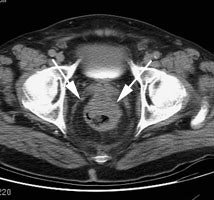

Recurrent colorectal carcinoma: The patient had prior resection for a rectal carcinoma and presented with a rising CEA. The CT scan demonstrated a soft tissue abnormality posterior to the urinary bladder that was interpreted as post operative scarring (white arrows). The CEA scan demonstrated a focal abnormality in the pelvis (black arrows) corresponding to the CT finding. At surgery this proved to be recurrent rectal carcinoma. |

|